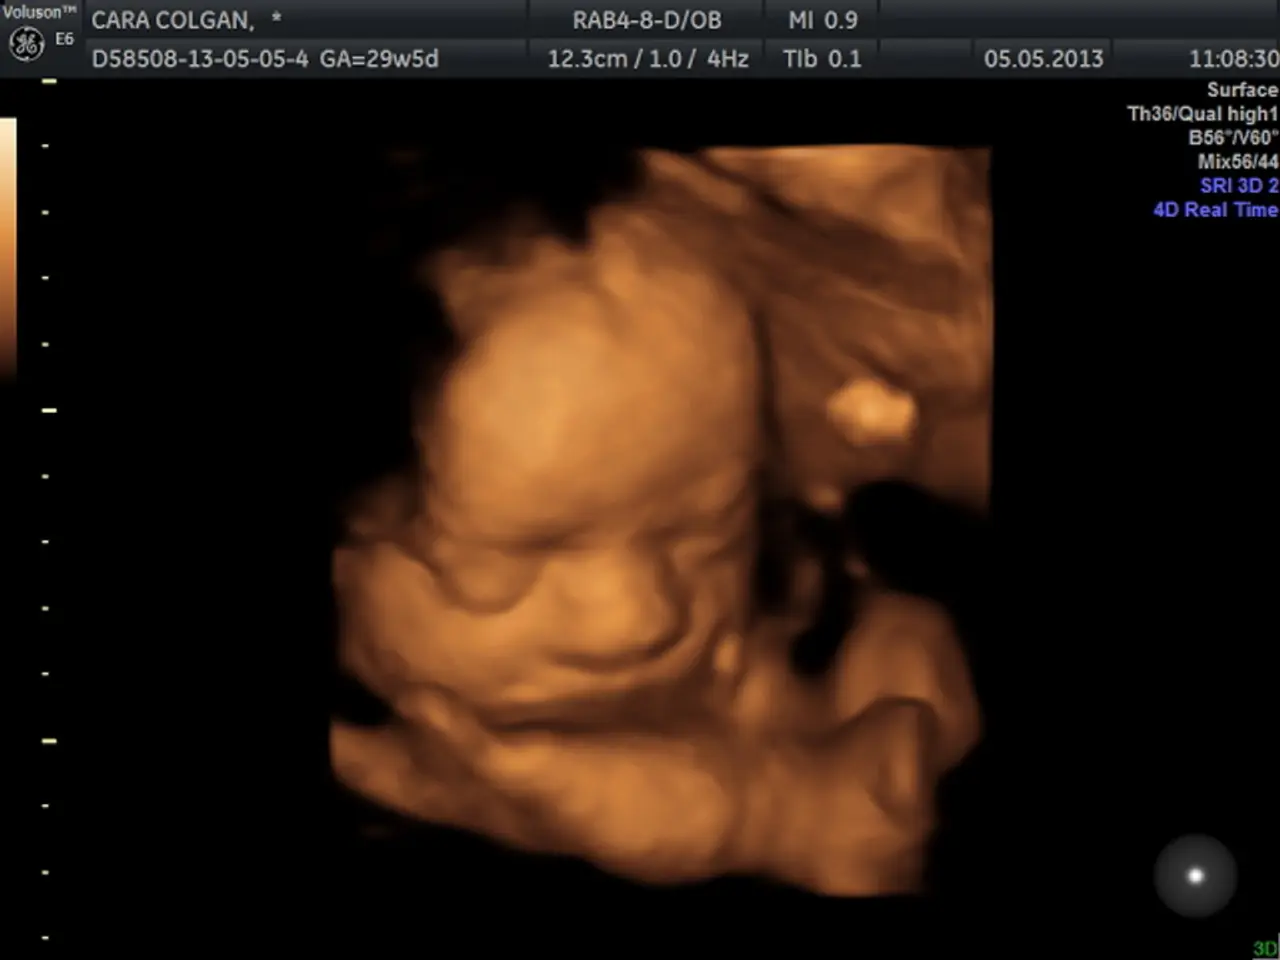

Under the Analar Saulygy (Maternal Health in Kazakh) project, Kazakhstan is developing new approaches including organ-preserving surgeries and enhanced postpartum care. Fetal surgery is also being developed to save infants before birth. New medications for pregnant women with chronic conditions have been added to the national formulary, and pregnant women now receive proactive digital notifications for screenings and appointments.